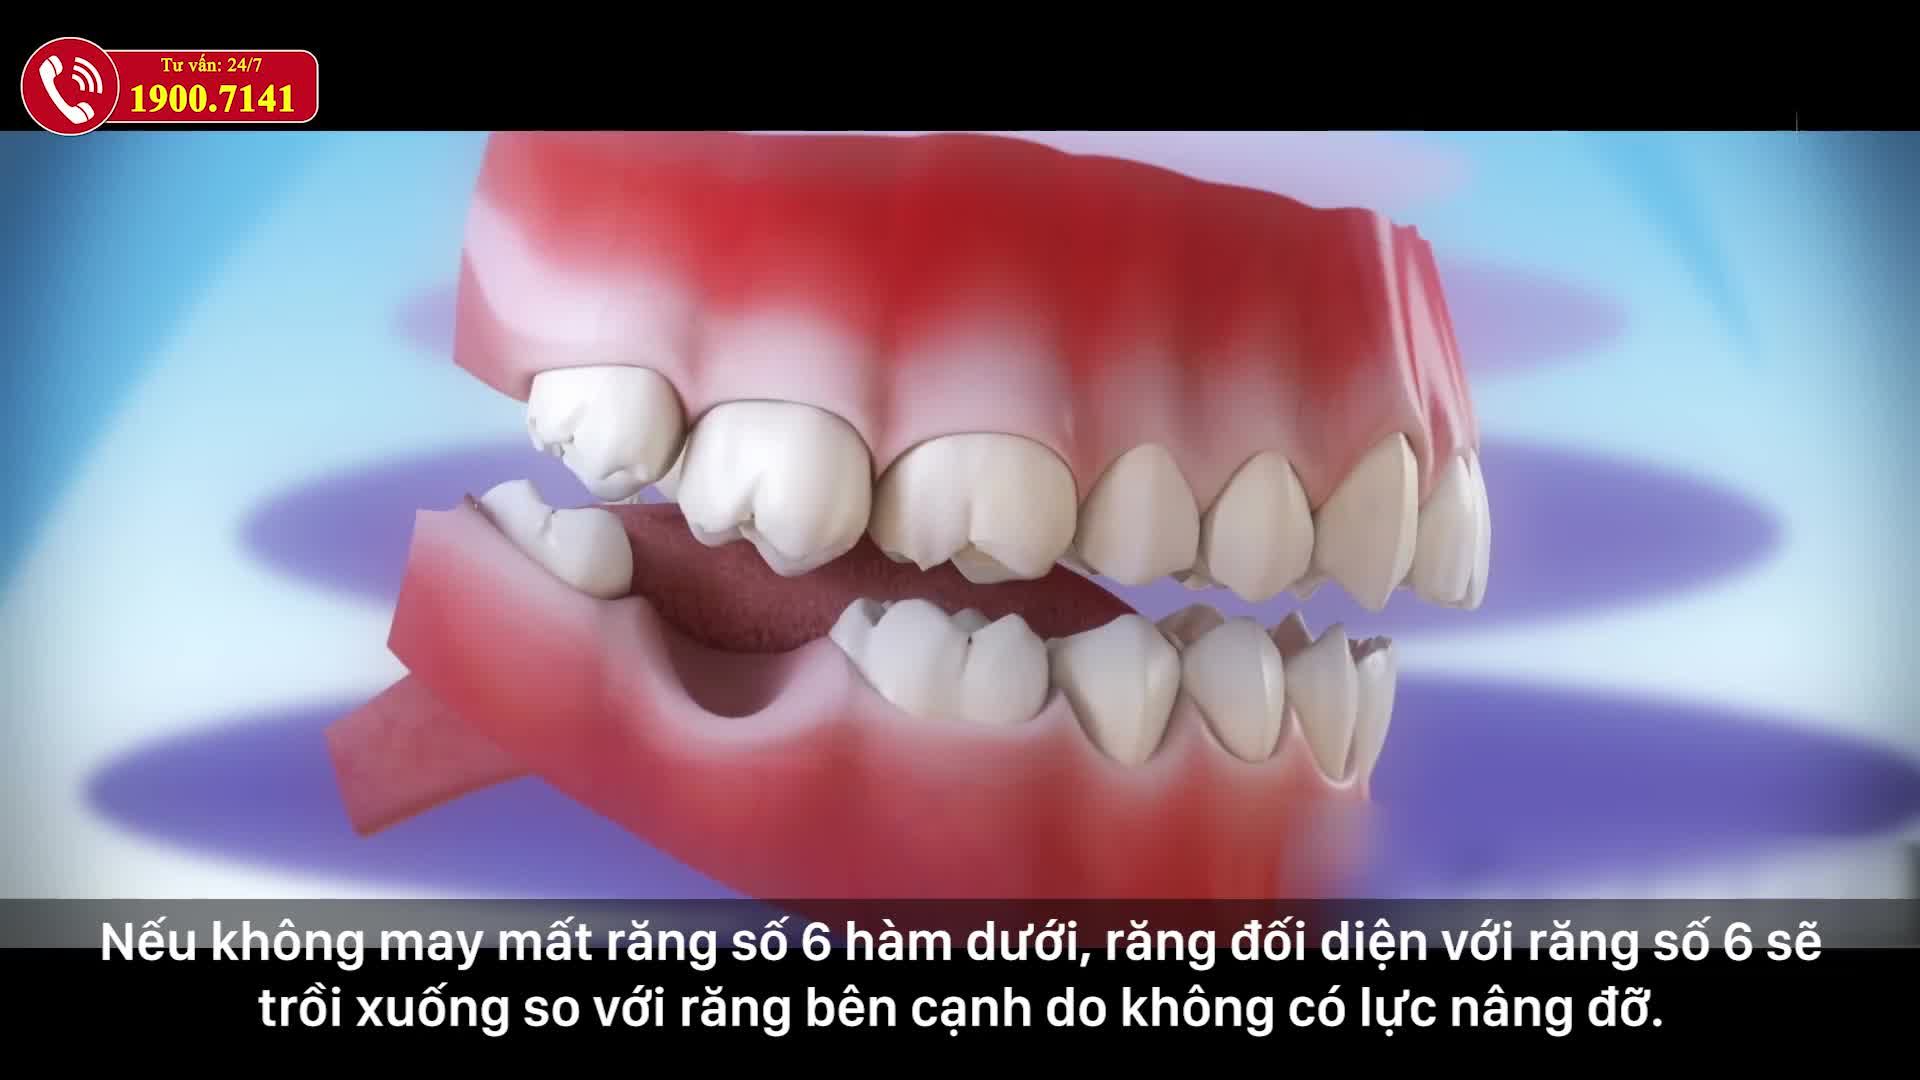

Trồng răng Implant là một kỹ thuật khó đòi hỏi tay nghề cao, chuyên môn sâu và dày dạn kinh nghiệm. Vì thế các khách hàng thông thái cần lựa chọn đúng cơ sở uy tín để thực hiện phẫu thuật, tránh xảy ra sai sót.